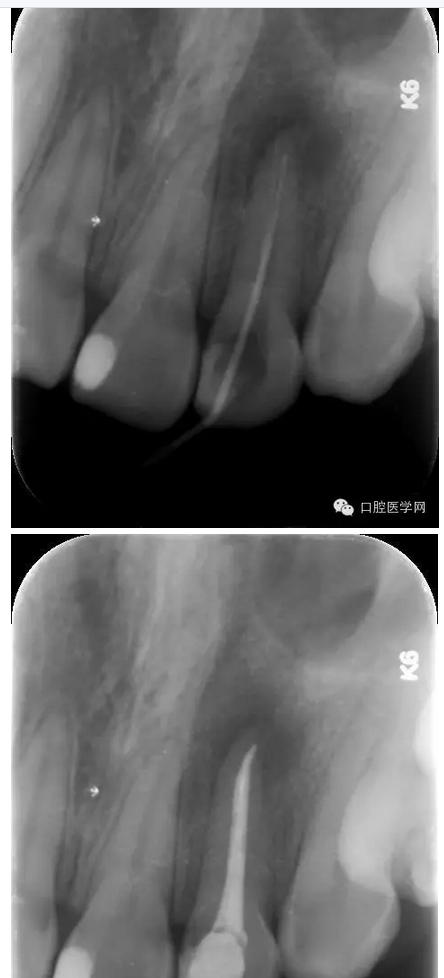

治療:第一次:去舊充填體,去腐質(zhì),GG鉆去除牙膠充填體,疏通根管,測(cè)量工作長(zhǎng)短,H銼與K銼去除剩余牙膠,雙氧水和鹽水大量沖洗,機(jī)擴(kuò)至S1,超聲蕩洗,激光行根管消毒,封CP球。

第二次:復(fù)診無(wú)不適,回去后疼痛即刻解除。叩診無(wú)不適。無(wú)松動(dòng)。處置:去暫封,見(jiàn)根管內(nèi)無(wú)滲出,機(jī)擴(kuò)至F2,雙氧水和鹽水大量沖洗,超聲蕩洗,激光蕩洗加消毒,干燥,封氫氧化鈣。

第三次:復(fù)診無(wú)不適。叩診無(wú)不適,無(wú)松動(dòng)。處置:去除暫封物,鹽水沖洗,試尖,牙膠尖+AHplus糊劑冷測(cè)壓充填,玻璃離子體充填。